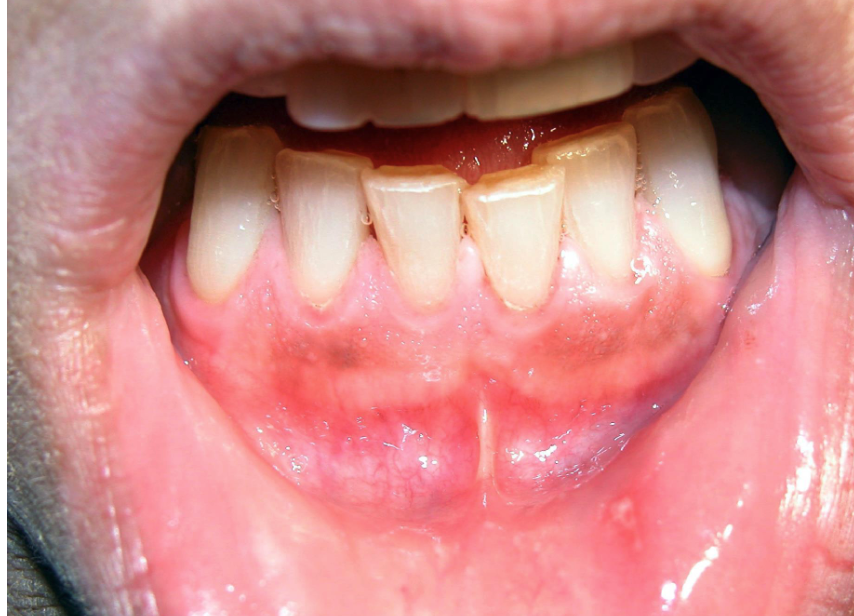

what is this

Burton line: indicating heavy metal toxicity